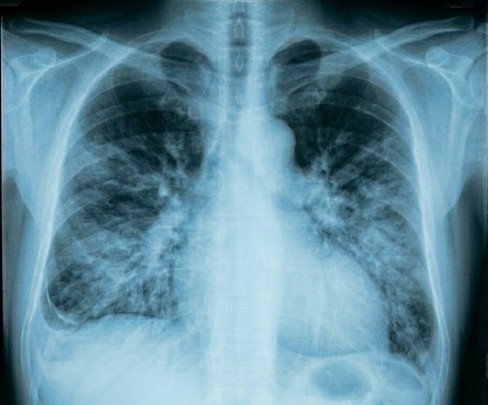

Pneumanosis is an AI-powered chest X-ray abnormality screening system that helps health professionals prioritize critical cases. Upload a chest X-ray and instantly get:

• Multi-abnormality detection across 14 conditions (5 active, 9 in development), each with a confidence score.

• Tier-based triage ranking that surfaces the most critical patients first, using a clinically-informed 5-tier severity system (from life-threatening to routine).

• Grad-CAM heatmap overlays that visually highlight where on the X-ray the model is flagging — so clinicians can see why the AI made its call.

• Side-by-side comparison for tracking a patient's progression over time or comparing two patients.

• AI-generated explanations with clinical recommendations for each finding.

The dashboard offers four views: a Patient Overview with floating annotation cards and bezier-curve connectors to flagged regions, a Triage Queue ranked by severity, a Compare view for longitudinal or cross-patient analysis, and an Upload page with drag-and-drop instant analysis.

• ML Model: We fine-tuned a DenseNet-121 on the NIH Chest X-ray dataset (112,120 frontal-view images across 30,805 patients). The model outputs multi-label binary predictions for the CheXpert Competition 5 conditions: Atelectasis, Cardiomegaly, Consolidation, Edema, and Pleural Effusion. Grad-CAM provides the explainability layer.